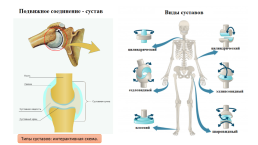

Диаграммы и схемы движения в суставах человека